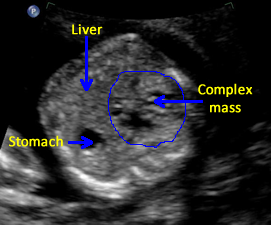

Above. Heterogeneous hepatic tumor mass with areas of calcification. Case 3.